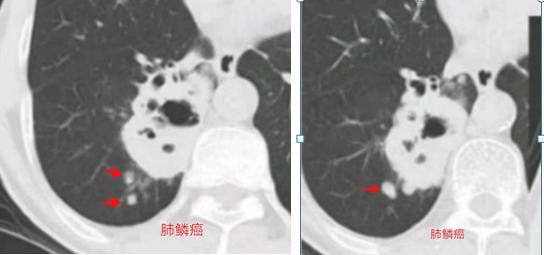

的确,肺癌容易发生转移,包括远处转移和邻近播散,但肺癌的邻近播散的形态跟卫星灶不同,常常都比较圆,就像同一类种子长出的果子,形态单一。比如下图:

这是一位肺鳞癌病人,病灶旁边有几个小圆形结节,是肿瘤播散种植,形态单一。